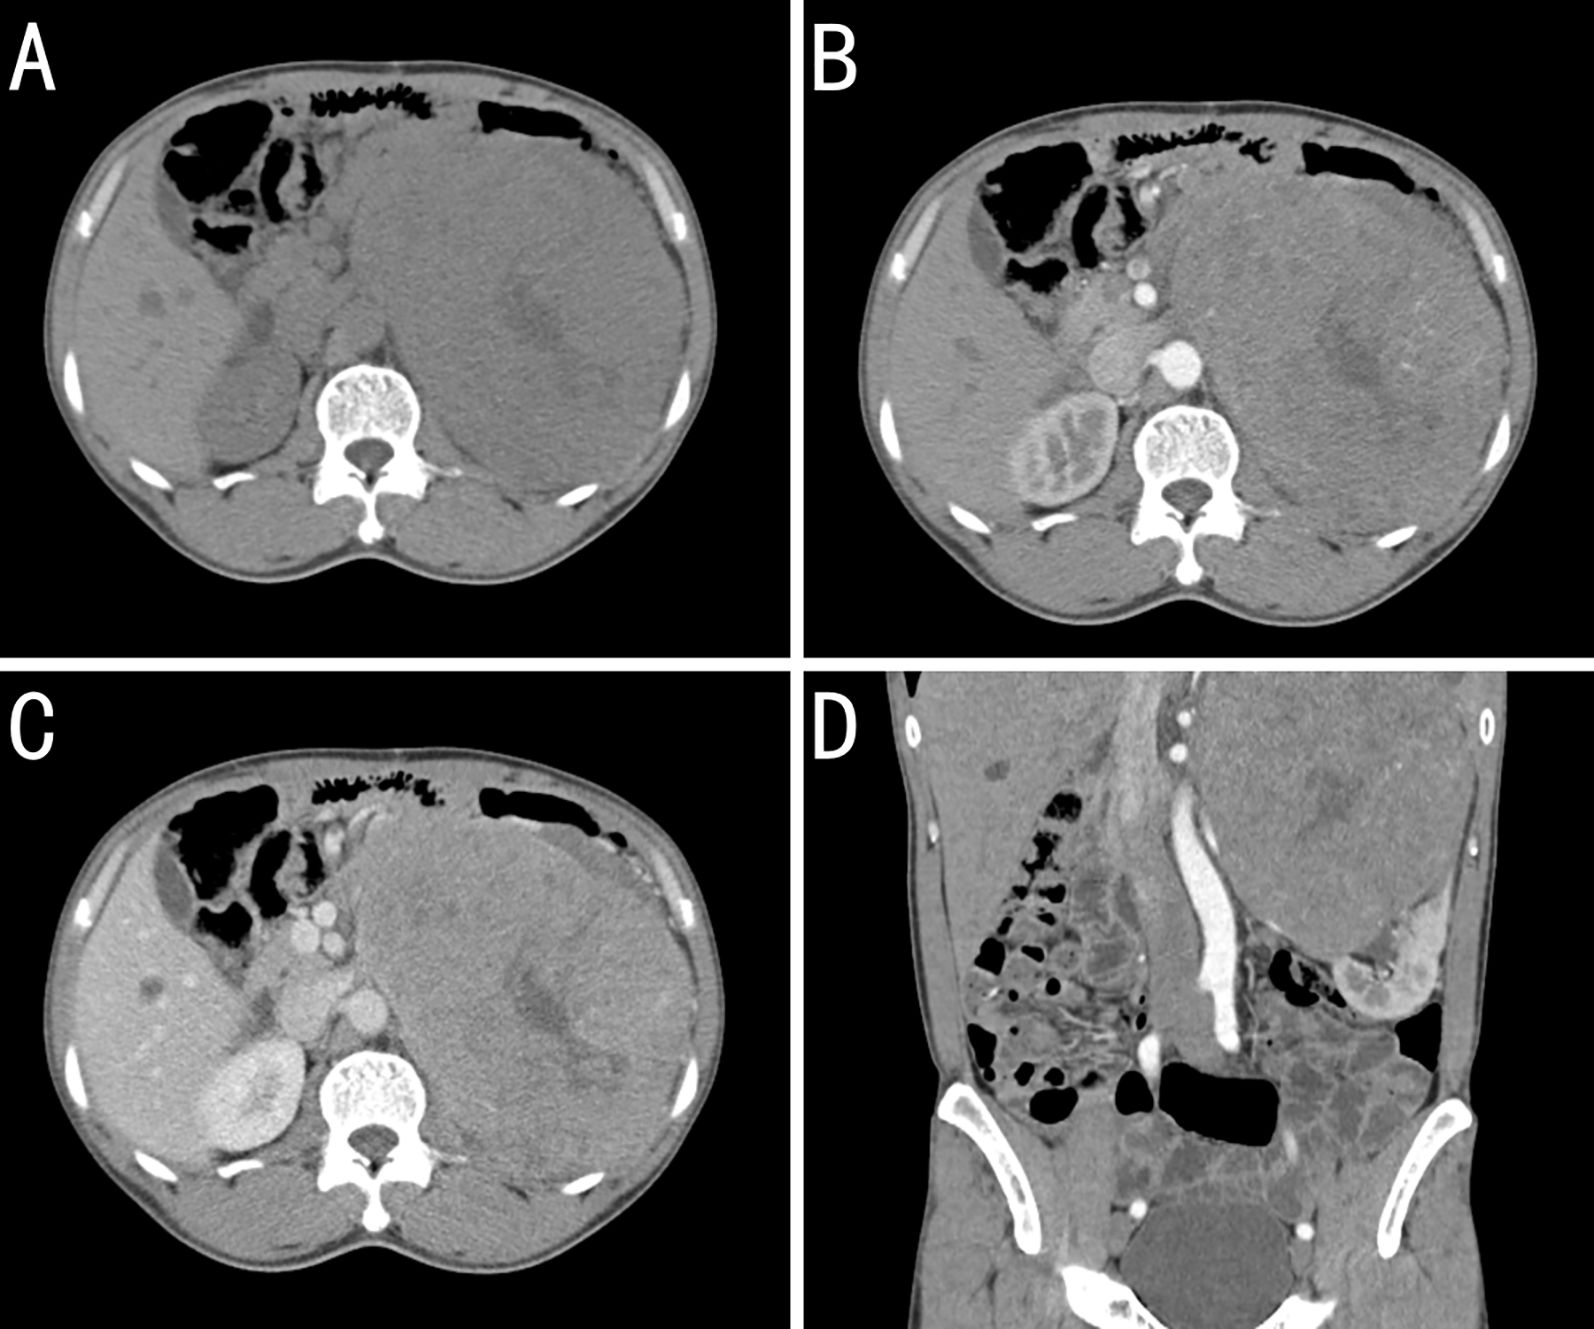

On October 24, 2020, retroperitoneal computed tomography (CT) revealed a left retroperitoneal mass measuring 16.3 × 12.0 cm with relatively well-defined margins abutting the left kidney. Heterogeneous low-density areas were present, and contrast enhancement was uneven. However, no enlarged regional lymph nodes were observed. Retroperitoneal CT revealed a large left-sided retroperitoneal mass, suspected to be of renal origin (renal carcinoma), and magnetic resonance imaging (MRI) with contrast was recommended (Figure 2).

Figure 2. Contrast-enhanced computed tomography (CT) findings for a kidney-metastatic gastrointestinal stromal tumor (GIST). (A) Plains showing a large left retroperitoneal mass of near-equal attenuation containing patchy low-density foci. (B) Arterial phase image revealing mild heterogeneous enhancement with multiple tortuous arteries and intralesional arteries, whereas the low-density foci remain unenhanced. (C) Venous-phase image showing continued enhancement of the solid components, whereas the low-density areas seen on the plain scan remain unenhanced. (D) Coronal arterial phase reconstruction showing the arterial supply from branches of the left renal artery. The mass obscures the boundary with the upper pole of the left kidney, which is compressed and displaced inferiorly.

On October 27, 2020, contrast-enhanced MRI confirmed a left renal mass measuring 15.7 × 13.6 cm with a slightly lower signal on T1-weighted images, a heterogeneously high signal on T2-weighted images, and fat-suppressed sequences showing restricted diffusion on diffusion-weighted images, with marked heterogeneous enhancement during the arterial phase and reduced enhancement in the parenchymal phase. Collectively, these findings provided strong evidence of malignancy.